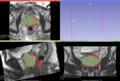

2015 Multi atlas based prostate segmentation

• Automatic segmentation of prostate gland on MRI data for preoperative planning and/or guided biopsy.

• Preliminary results (before project week):

Dice coefficient: median = 0.704

5° percentile = 0.485

95° percentile = 0.850

Average Hausdorff Distance (mm): median = 3.691

5° percentile = 1.790

95° percentile = 7.124

95° percentile Hausdorff Distance (mm): median = 8.903

5° percentile = 4.988

95° percentile = 17.498

Required time:

roughly 10 minutes per case.